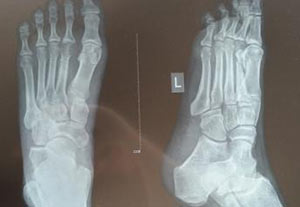

(图:王先生到院时,左足第一跖趾痛风石明显)

查体:左足第一跖趾可见痛风石形成,且红肿、触痛,可见右足第一跖趾2cmx1.5cm痛风结石形成。

(图:经过科学方案治疗,王先生左足现已恢复正常)

在接受第一个疗程治疗后,王先生的左足红肿症状明显减轻,疼痛感也有了明显的改善,双足也能下地慢慢行走。第二个疗程结束后,王先生皮温恢复正常,左足第一跖趾痛风石逐渐减小,趾关节及脚背红肿基本消失,按压还有微痛感。第三个疗程结束后,王先生左足红肿症状消失,无疼痛感,行走自如,右足第一跖趾关节受损得以恢复。